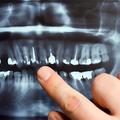

Rentgensko slikanje zob lahko škodi možganom

Zaradi rentgenskega slikanja zob imate lahko dvakrat več možnosti, da zbolite za rakom na možganih, ugotavlja najnovejš…